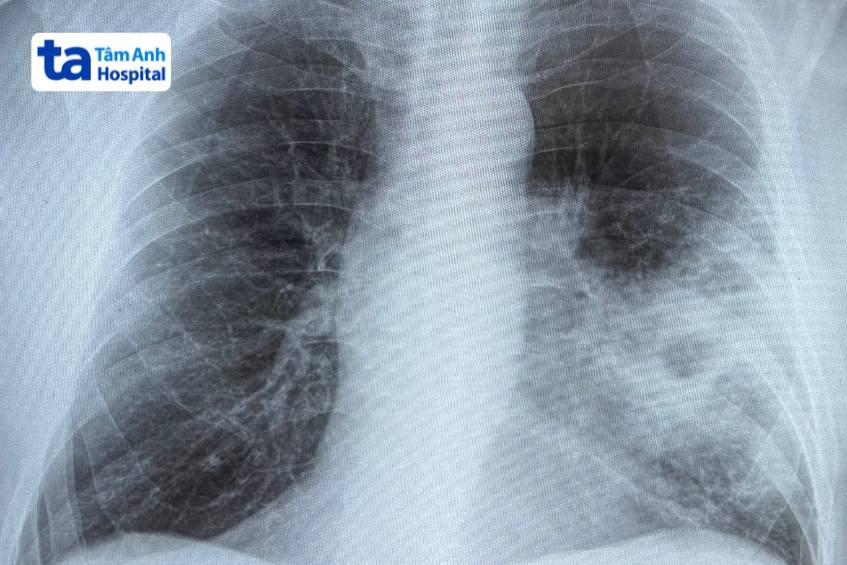

X-quang: Hình ảnh “đám mờ” khi chụp X-quang là “tiêu chuẩn vàng” trong việc chẩn đoán. Tuy nhiên cần lưu ý 2 trường hợp sau:

Dương giả: Có “đám mờ” nhưng không phải bệnh viêm phổi. Cần chẩn đoán phân biệt với bệnh do nguyên nhân không nhiễm trùng (viêm mạch máu, phản ứng thuốc), bệnh phổi mô kẽ, phù phổi cấp do suy tim ứ huyết/hẹp hai lá, nhồi máu phổi, xuất huyết phế nang, xẹp phổi, ung thư phế quản – phế nang.

Âm giả: Không (hoặc chưa) thấy “đám mờ” nhưng vẫn là bệnh viêm phổi. Thường gặp trong các trường hợp: giai đoạn rất sớm của bệnh (chưa đủ thời gian hình thành tổn thương trên X-quang), người bệnh mất nước nặng, giảm bạch cầu hạt trung tính (làm giảm phản ứng viêm), hoặc bệnh do Pneumocystis jirovecii ở người bệnh suy giảm miễn dịch nặng (như AIDS). Trong các trường hợp này, tổn thương thường lan tỏa dạng kính mờ, khó thấy trên phim chụp X-quang thông thường.

Hình ảnh X-quang viêm phổi nặng bên trái ở người bệnh.